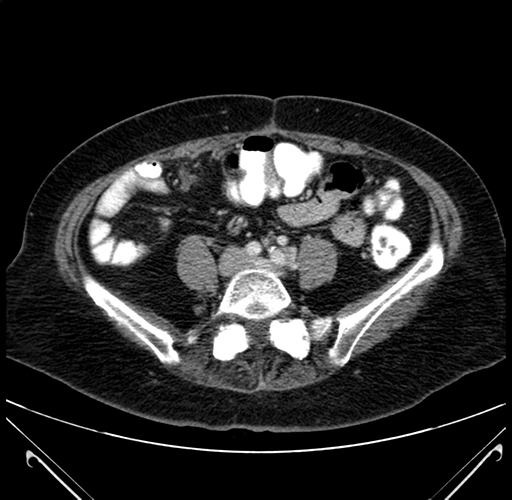

Pre-Chemo: Coronal Venous

Coronal Venous

Imaging analysis

Based on your CT findings, which issue(s) would give reason for "planned slowing down moment(s)" in this case?

Considering a standard right hepatectomy procedure, what step(s) of the operation would you do differently in this case?